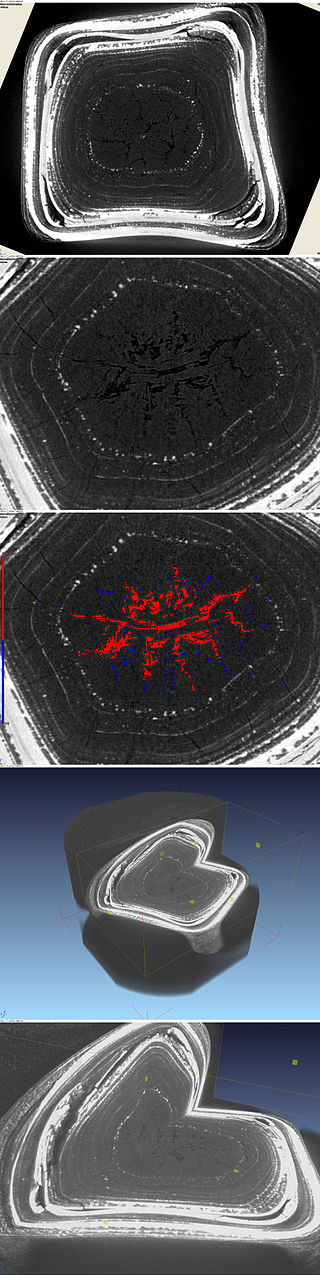

Porcelain gallbladder is a complication of late stage chronic cholecystitis.

Porcelain gallbladder is a shrunken, hard gallbladder because of chronic inflammation, fibrosis, and dystrophic calcification.

Porcelain gallbladder findings vastly increases the risk for carcinoma of the gallbladder.

Cholecystectomy is the recommended course of action for chronic cholecystitis, especially if a porcelain gallbladder is present.